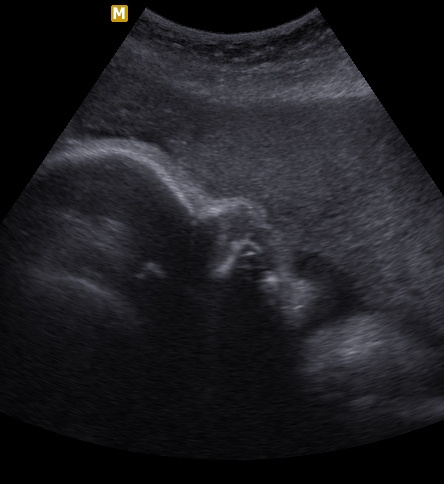

УЗИ 32-34 недели

Вот такое у меня сокровище стеснительное, Уткнулся в плаценту и еще пуповину рядышком держал)) Зато свои мужские дела не стесняясь показал. Врача спрашиваю, а там точно мальчик? Он говорит, мол я пока не смотрел...хотя...ну да, точно мальчик, вон какие богатства развесил))))

Беременность 34 недели и 2 дня (по данным фетометрии), 33 недели и 4 дня (по последней дате месячных)

Степень зрелости плаценты 1

Толщина плаценты 32 мм

Расположение плаценты по передней стенке

Все органы малыша визуализируются и обозначаются кучей цифр))) Но в общем - все ок! Ну, если слазить в интернет и посравнивать нормы, то меня смутила немного длина костей носа - всего 7,9 мм. А по идее должно быть почти 9 уже. Но, наверно, вот такой курносик вырос у Леоника, догонит мамин и папин нос в подростковом возрасте, а пока - пусть радуется своей крохотульке)))

ЧСС 146 Дали послушать

Предпологаемый вес плода 2611 гр.

Ого, какие мы большущие!! Узист сказал, что к сроку родов должны быть примерно 3800. Слонопотамик там у меня)))